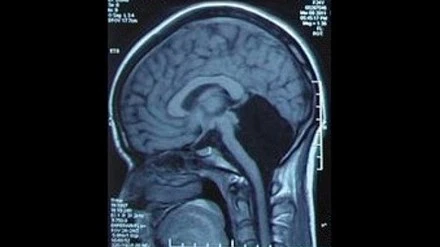

Một phụ nữ, 24 tuổi, ở tỉnh Quảng Đông, Trung Quốc phải nhập viện vì cảm thấy chóng mặt và buồn nôn. Sau khi chụp não, các bác sỹ của bệnh viện quân đội Quảng Đông hết sức ngạc nhiên khi phát hiện cô không có tiểu não (phần màu đen trong ảnh), tức là thiếu một nửa não bộ mà vẫn có thể sống bình thường.

Tiểu não nằm ở trung tâm hộp sọ, chứa khoảng một nửa số nơ ron thần kinh, khu vực chỉ huy việc cân bằng cơ thể, chạy nhảy, đá bóng và ngôn ngữ.

Do thiếu tiểu não, nên đến 6 tuổi cô mới biết nói, 7 tuổi mới biết đi. Các cuộc kiểm tra cho thấy, cô có thể hiểu được các từ, nhưng gặp khó khăn khi phát âm, giọng của cô hơi run run và phát âm không được chuẩn.

Hiện cô đã có gia đình và có một con gái. Rất may cô bé có bộ não bình thường. Đây là một trong số 9 người trên thế giới mắc căn bệnh hiếm gặp này. Các bác sỹ tin rằng, các chức năng của tiểu não của cô có thể đã được thay thế bởi vỏ não.